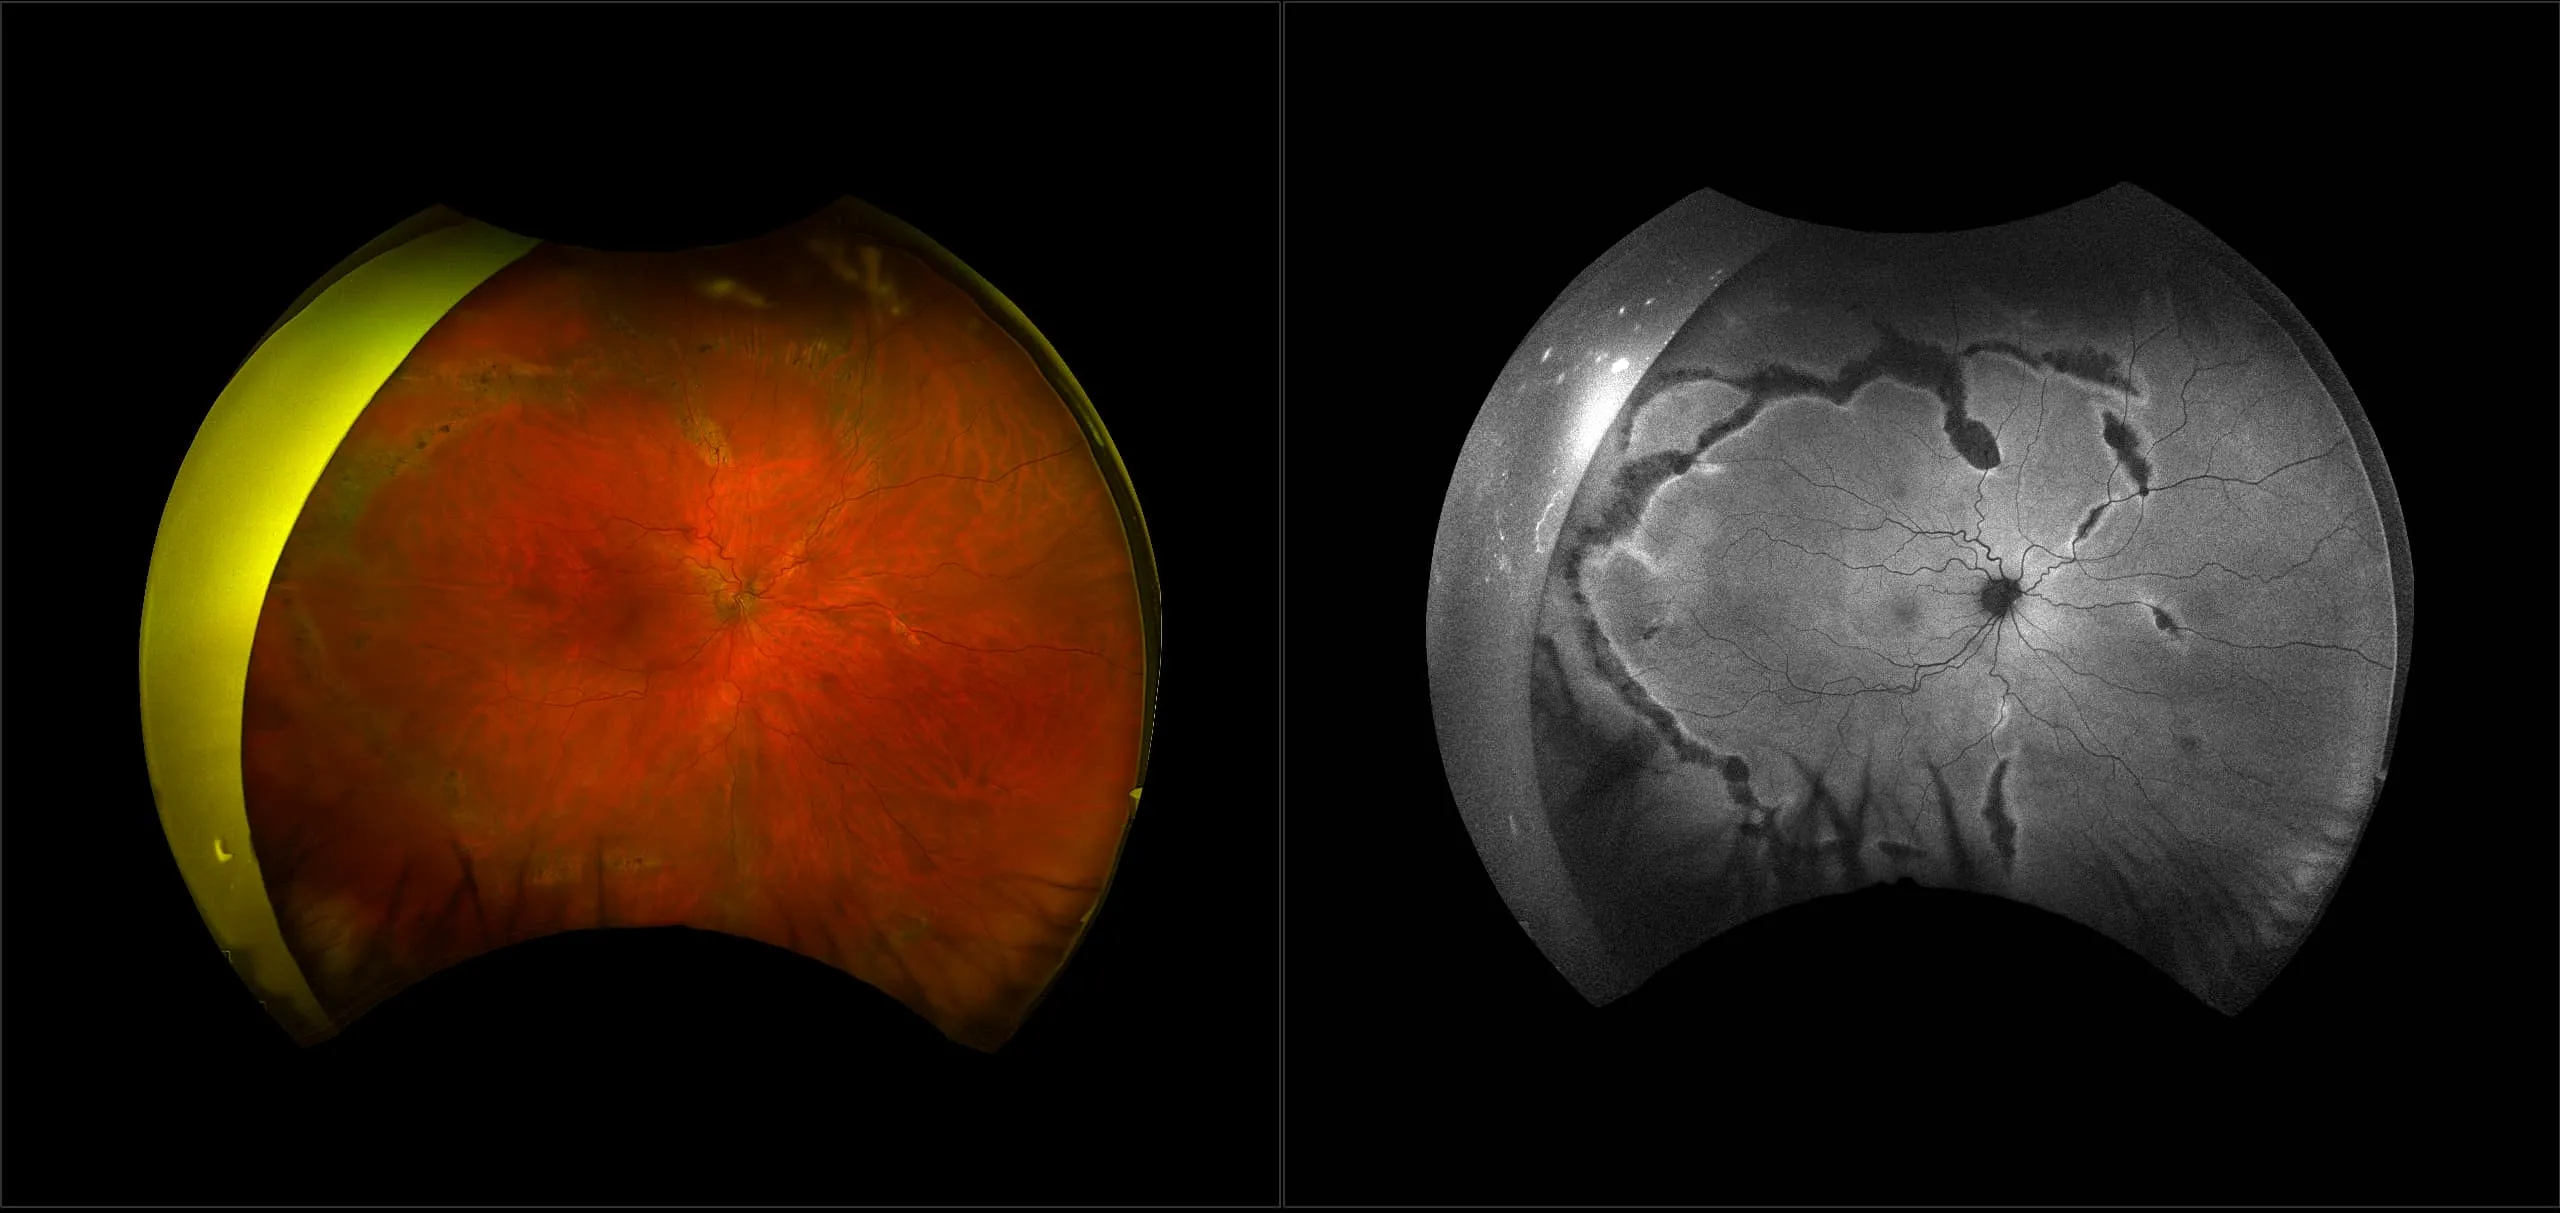

optomap® Recognizing Pathology

This material is designed as a searchable reference resource to support clinical decision-making. The information contained here should be used as general guidance when viewing optomap and OCT images from Optos devices. The differential diagnosis should be made under the direction of the responsible physician. These images were taken on the latest ultra-widefield optomap devices.

The Cases and Images

optomap Recognizing Pathology is searchable by pathology and/or optomap image modality. You may search by multiples of each selection. Each individual case is represented by the accompanying thumbnail image. Most cases include several different optomap image modalities. To view a full description of the case, please click on the thumbnail. Each image in the case will be made available through our OptosAdvance software which provides multi-dimensional visualization of digital images to aid in the analysis of anatomy and pathology. Support and pathology definitions can be found by selecting one of the buttons, above. Should you have questions, please complete the form below.